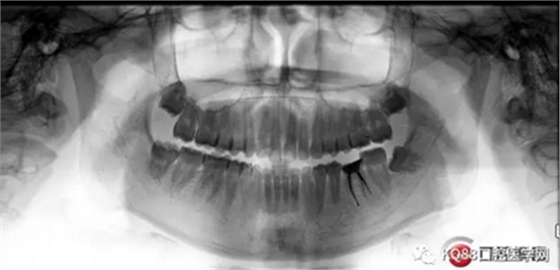

X-ray:36根尖云霧狀低密度影,根分叉未見異常。

診斷:36慢性增生性牙髓炎。

第四步:試尖片。四個根管,錐度良好,牙膠尖到位。